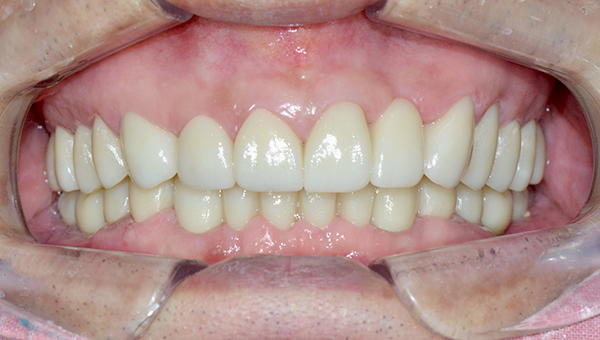

강*란 임플란트 시술 사례

전체 임플란트

2025.02.07

치료 전

2025.08.19

치료 후